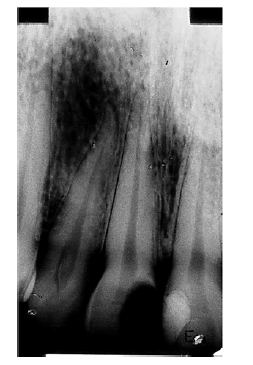

Com base na imagem da radiografia apresentada e nos conhecimentos relativos à histopatologia pulpar e periapical, julgue os itens a seguir.

O cisto periapical apresenta quatro componentes fundamentais: cavidade cística, revestimento epitelial, tecido extra epitelial e cápsula colagenosa. A cavidade contém tecido necrótico, algumas vezes, cristais de colesterol rachados e eritrócitos.